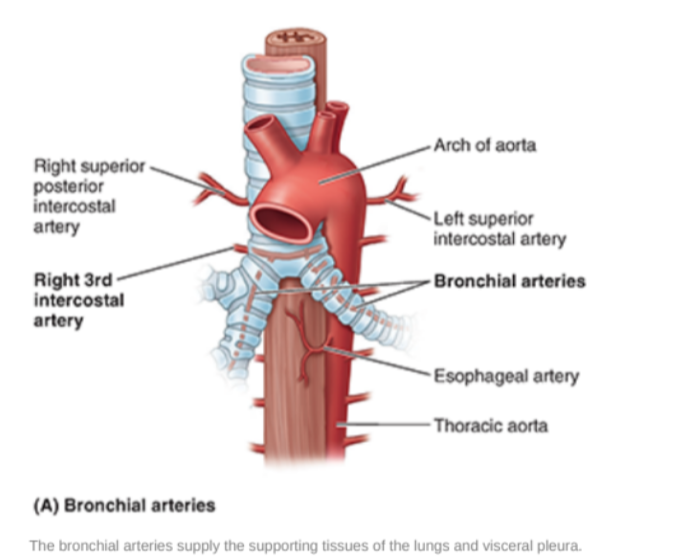

Bronchial arteries

Along. with the veins form part of the nutritive system of vasculature of the lungs

Interconnect within the lung with branches of the pulmonary arteries & veins

Originate from the thoracic aorta or one of its branches —

A singular right bronchial artery normally arises from the third posterior intercostal artery

Occasionally originates from upper left bronchial artery

2 left bronchial arteries directly arise from the anterior surface of the thoracic aorta —

Superior left bronchial artery arises — vertebral level TV

Inferior left bronchial artery arises inferior to left bronchus

They run on the posterior surfaces of the bronchi & ramify in the lungs to supply pulmonary tissues